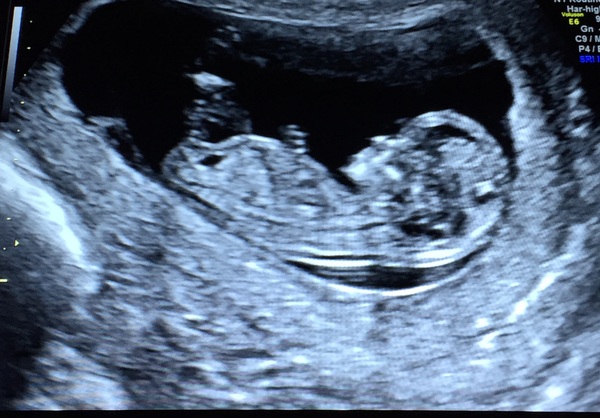

I had my scan today - another active one. Waved a hand and bounced which set me off giggling which didn't help... due date confirmed for 15th May.

Back from my successful scan - very wriggly baby is in there alright, just difficult to take in when you've barely had any symptoms. Low risk for the Trisomys so no Harmony needed. It was a fascinating experience and the hospital was so impressive that I've booked in for the 20 week scan there too.

Oops missed your scan power and peach! Lovely pic Smile

Great pic peach

Lovely scan peach